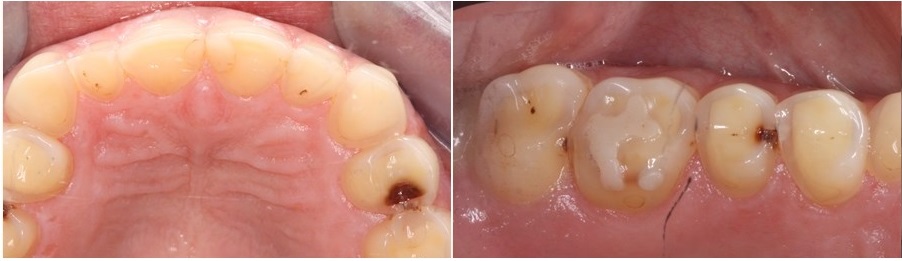

Βουλιμία και συνέπειες στα δόντιαΣτην διάβρωση των δοντιών οι περιοχές στις οποίες εντοπίζεται αρχικά το πρόβλημα είναι οι υπερώιες πλευρές των άνω πρόσθιων δοντιών (φωτογραφία αριστερά). Στα πρώιμα στάδια η βλάβη είναι πολύ δύσκολα αναγνωρίσιμη λόγω του ότι η θέση των δοντιών αυτών δεν είναι εύκολα ορατή στον ασθενή. Σιγά σιγά όμως η απώλεια οδοντικής ουσίας επεκτείνεται και στο κοπτικό χείλος των δοντιών τα οποία λεπταίνουν και κονταίνουν.

Στα προχωρημένα στάδια της νόσου εμφανίζονται αλλαγές και στα πίσω δόντια (φωτογραφία δεξιά) τα οποία καθώς διαβρώνονται μικραίνουν σε μέγεθος οδηγώντας τελικά σε απώλεια της κάθετης διάστασης του προσώπου. Χαρακτηριστικά σε αυτές τις περιπτώσεις τα σφραγίσματα που τυχόν υπάρχουν στα δόντια επειδή δεν διαβρώνονται, μένουν πιο ψηλά στην επιφάνεια των δοντιών ενώ η οδοντική ουσία γύρω από αυτά μειώνεται.